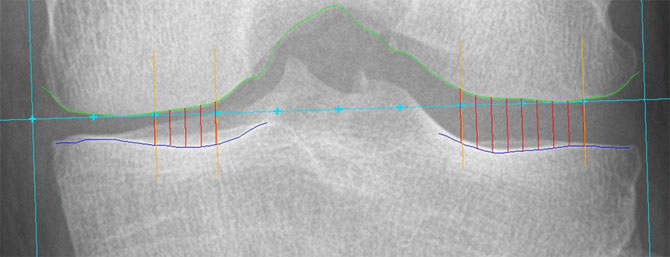

Radiographic JSW at fixed locations |

Hand JSW Measurement Five Measurement regions: JSW1, JSW2, JSW3, JSW4, JSW5 Central JSW measurement: JSWC = (JSW2+JSW3+JSW4)/3 |